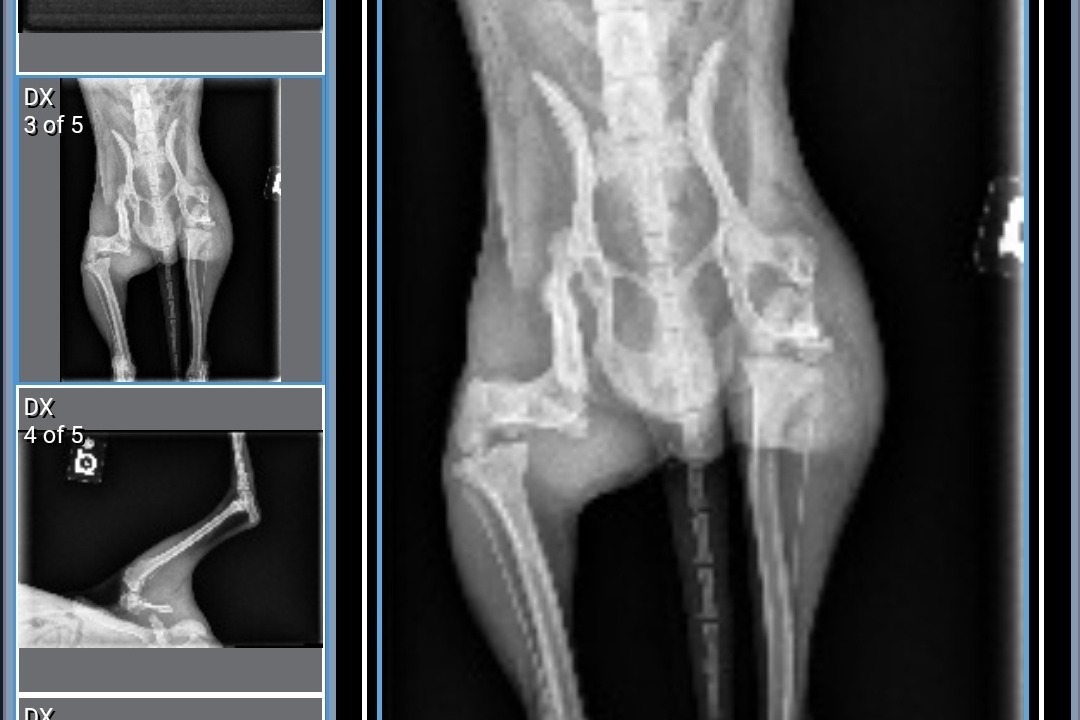

After x-rays, we found out that Mikko had two broken legs. One was an older fracture that had healed improperly and the other was more recent, his leg was completely detached and scraping against his muscle. Due to the fractures, Mikko suffered extensive muscle atrophy and has had to rely on his front legs for mobility. The doctors advised us to proceed with the surgery as soon as possible, stating, "There's still a chance to save his legs but if we wait, we will have to amputate."

The following images are Mikko's x-rays and the first documented photo of him when he was found.